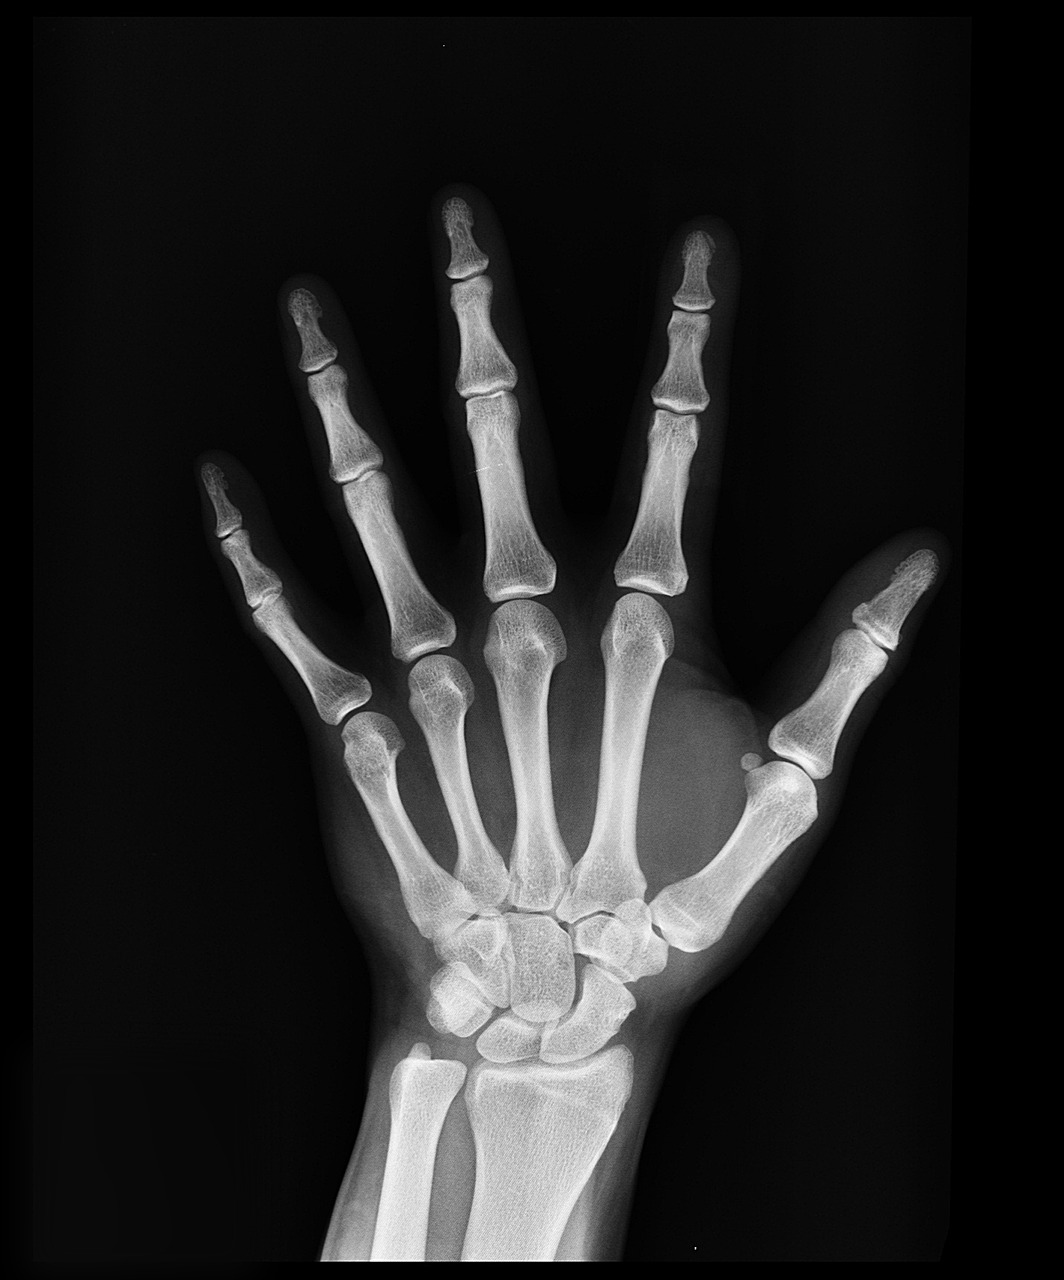

폐결핵을 위한 흉부 검사는 우리가 잘 알고있는 X-ray를 활용한 검사입니다. 보통 임산부의 경우 X-ray를 촬영하지 못하기 때문에 객담검사를 실시하기도 합니다.

전염성 피부질환은 양 손을 검사자한테 보여주는 방식으로 매우 간단합니다. 다만 유흥업소 종사자의 경우 결핵, 에이즈 검사 등을 진행하기도 합니다.